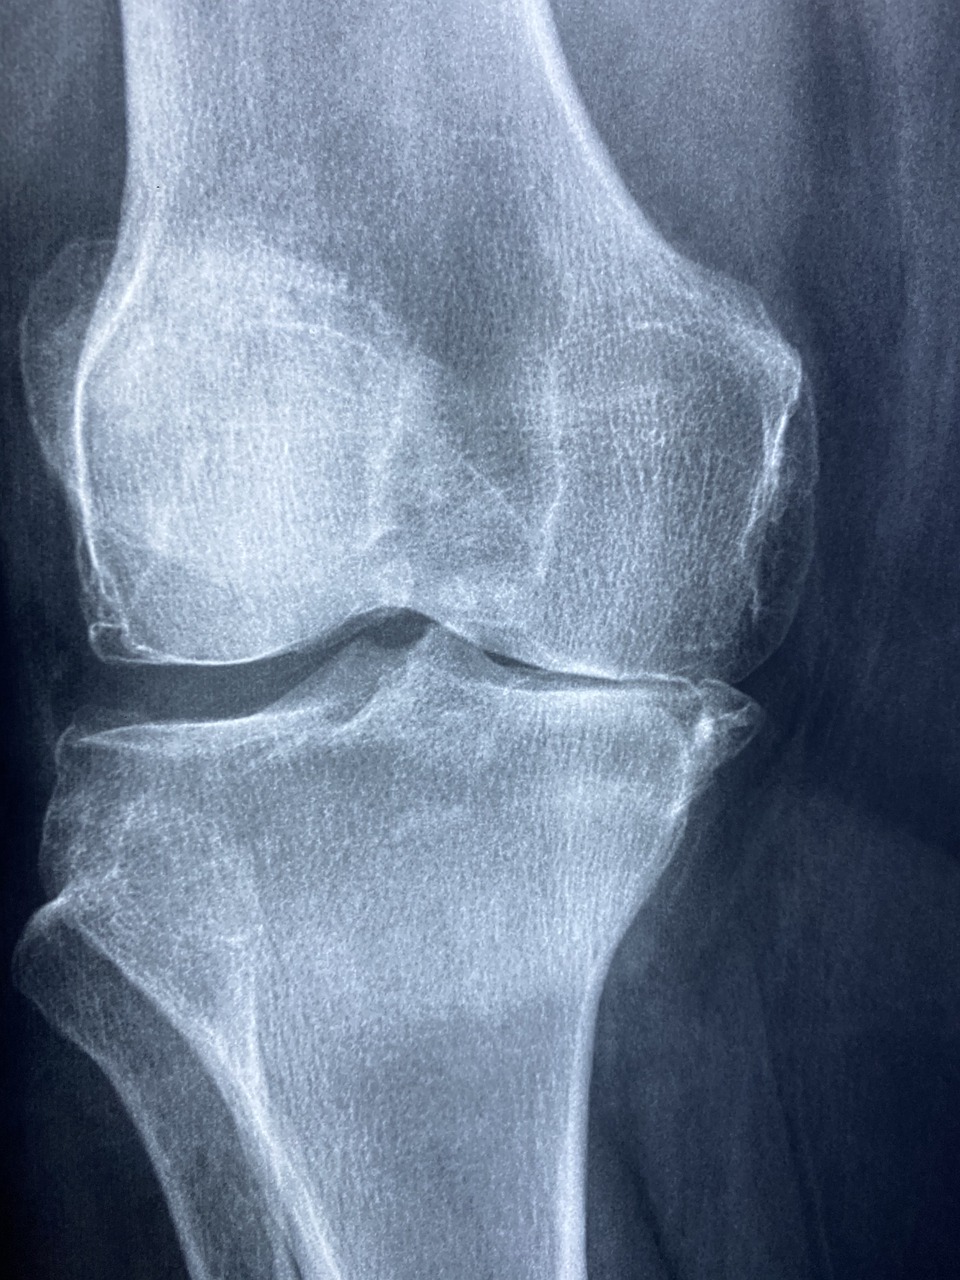

膝关节骨关节炎(KOA)骨关节炎是一类常见的退行性骨关节疾病,在中老年人群中常见。骨关节炎特征为滑膜关节的重要区域关节软骨的缺失,伴随有不同程度的骨赘形成、软骨下骨改变与继发的滑膜炎。膝骨关节炎的临床表现主要为关节进行性疼痛、肿胀、僵硬、活动受限、畸形。